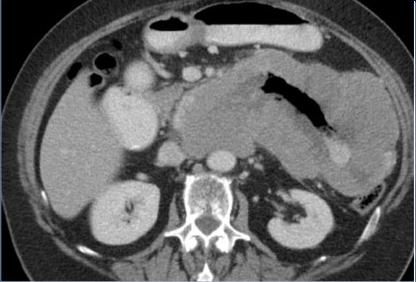

| Adeno carcinoma duodenum :

Epaissisement de la paroie duodenum en

circonferentielle , infiltrant et irreguliairement .

Image de stenose de la lumiere du portion lesionaire

. Image TDM en coupe axilae . |

Mema cas ( fleche

rouge ) en coupe cornale ( frontal )

|